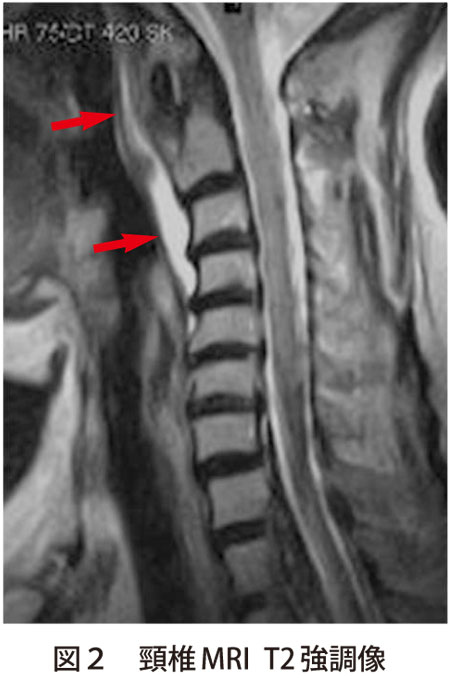

石灰沈着性頸長筋腱炎:急に痛くて首が回らない!つぐ脳神経外科・頭痛クリニック厚木市の脳神経外科即日MRI検査駐車場あり。

感染症との鑑別が困難な石灰沈着性頸長筋腱炎 - 医療法人信岡会 菊池中央病院。

石灰沈着性頚長筋腱炎 池田医院 整形外科。